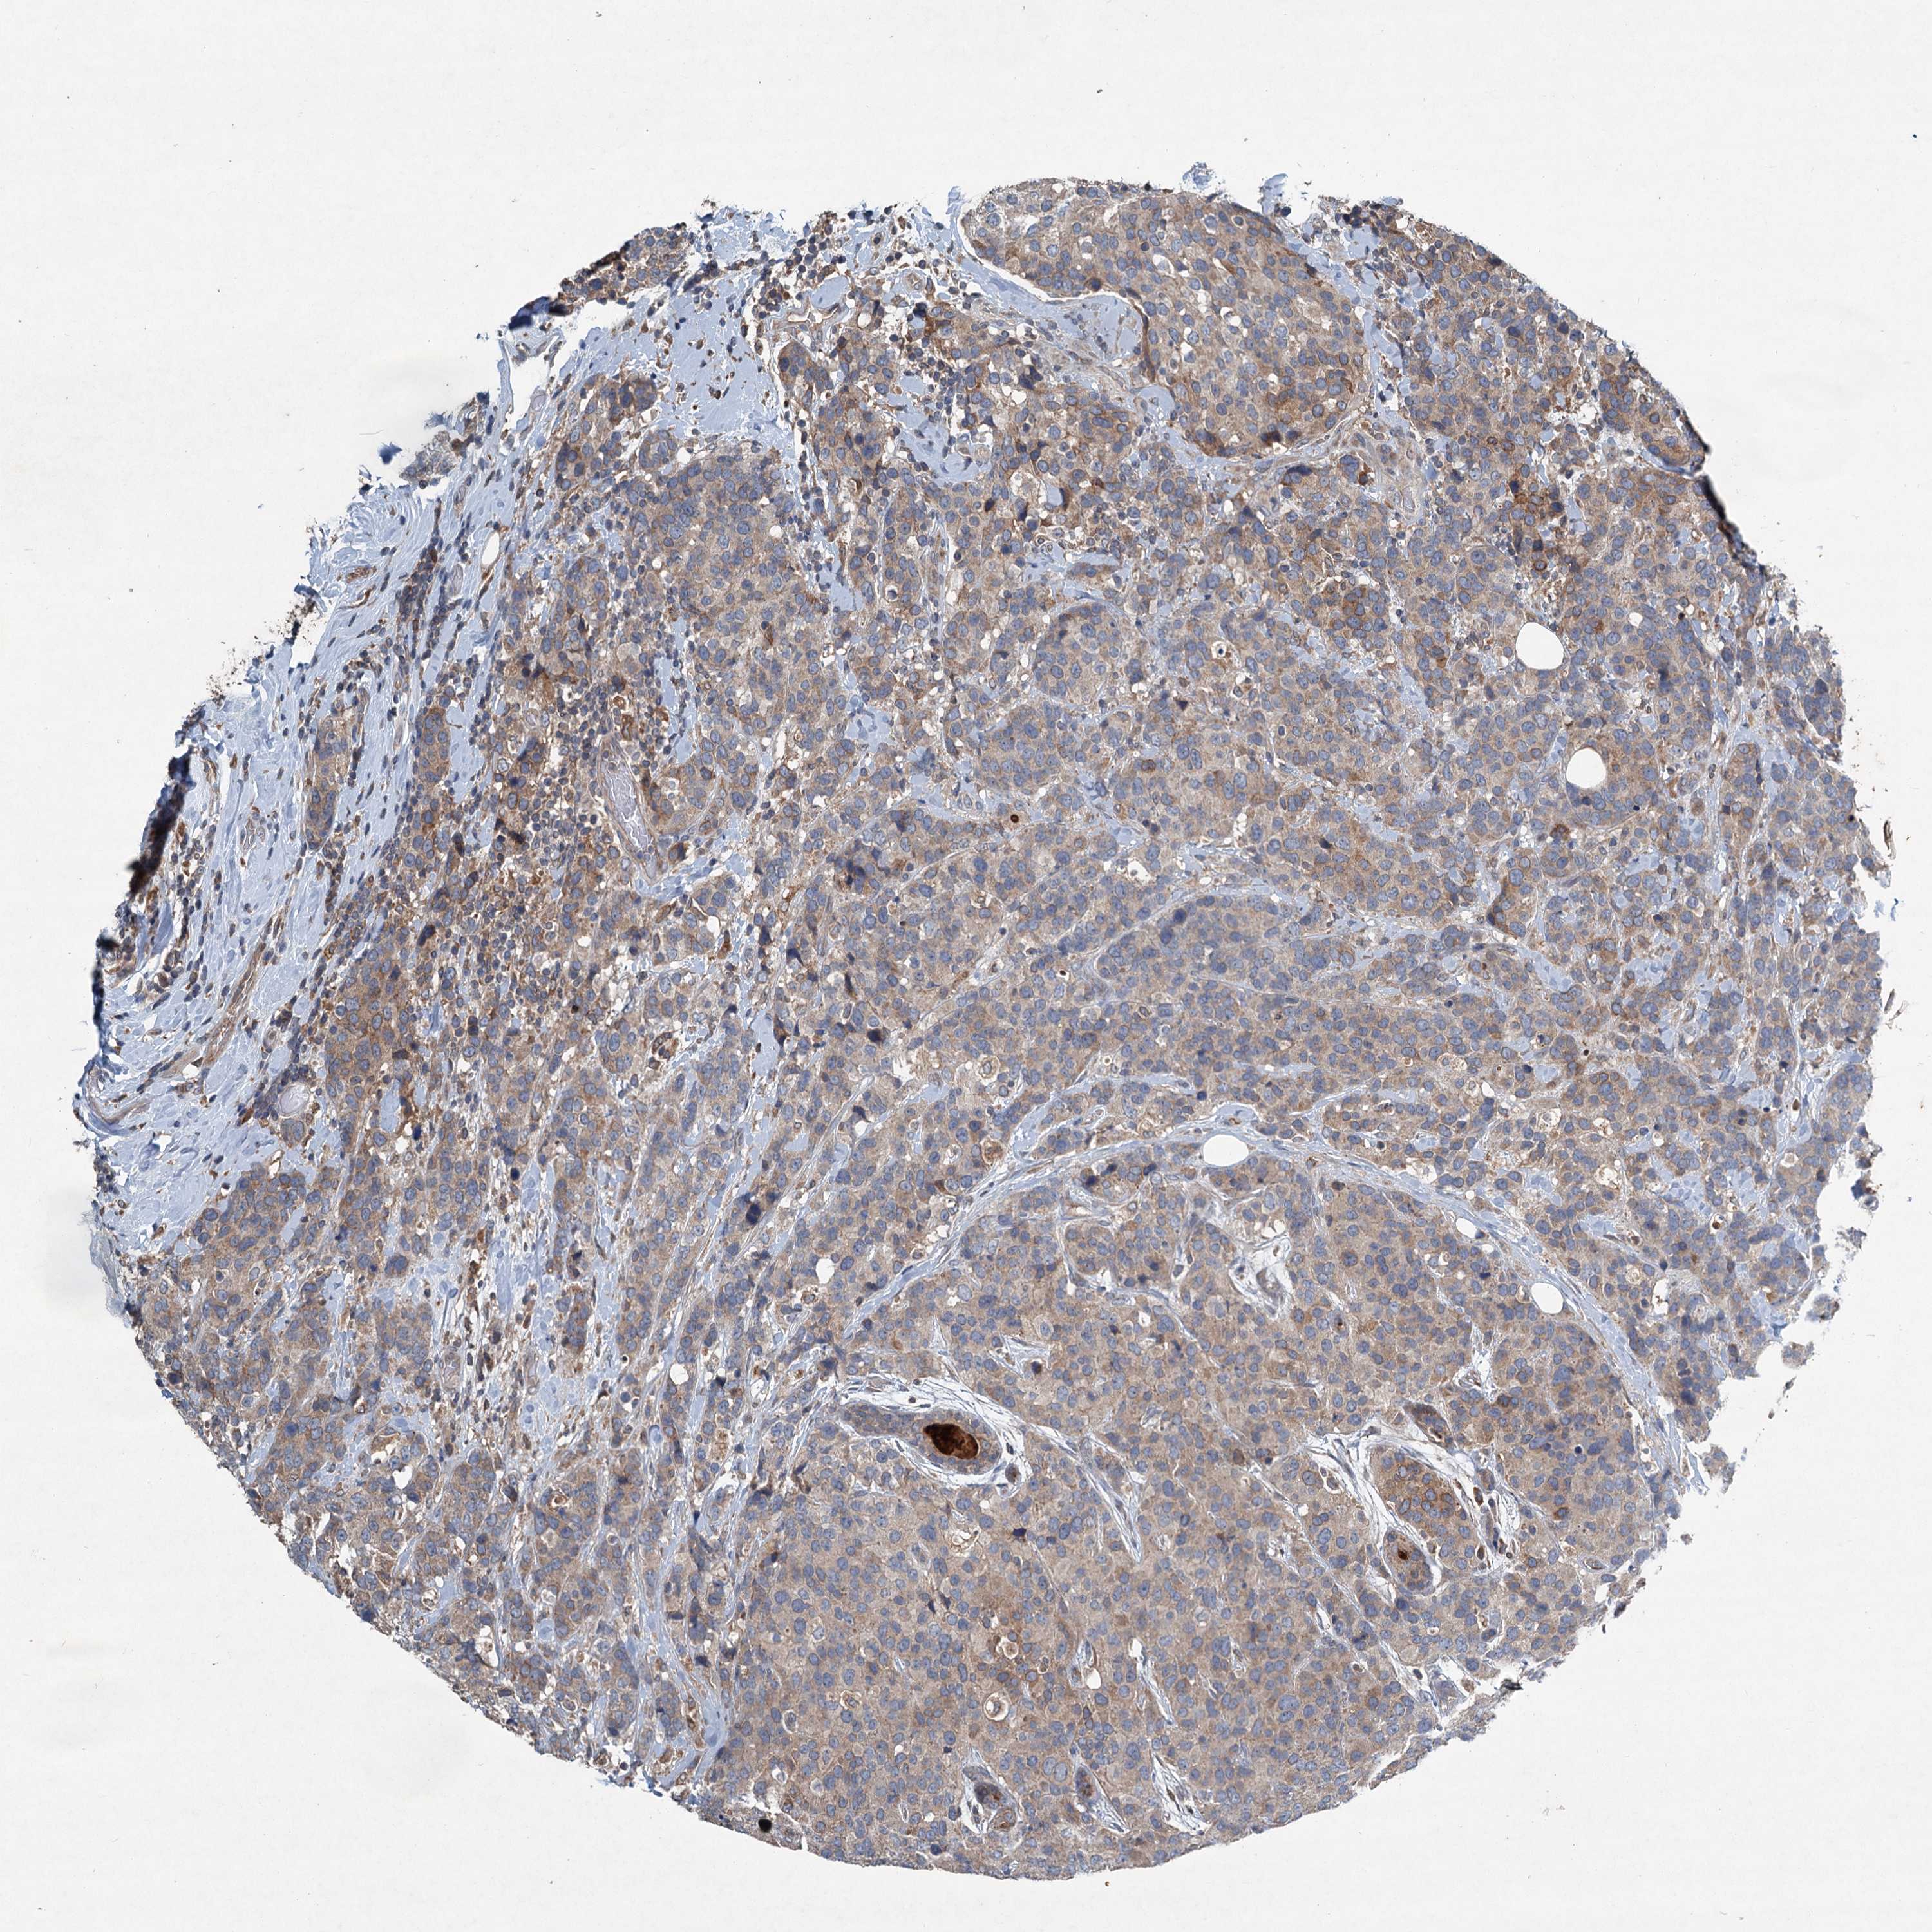

CANCER BREAST CANCER Show tissue menu

BRCA TCGA BRCA VALIDATION PROTEIN EXPRESSION